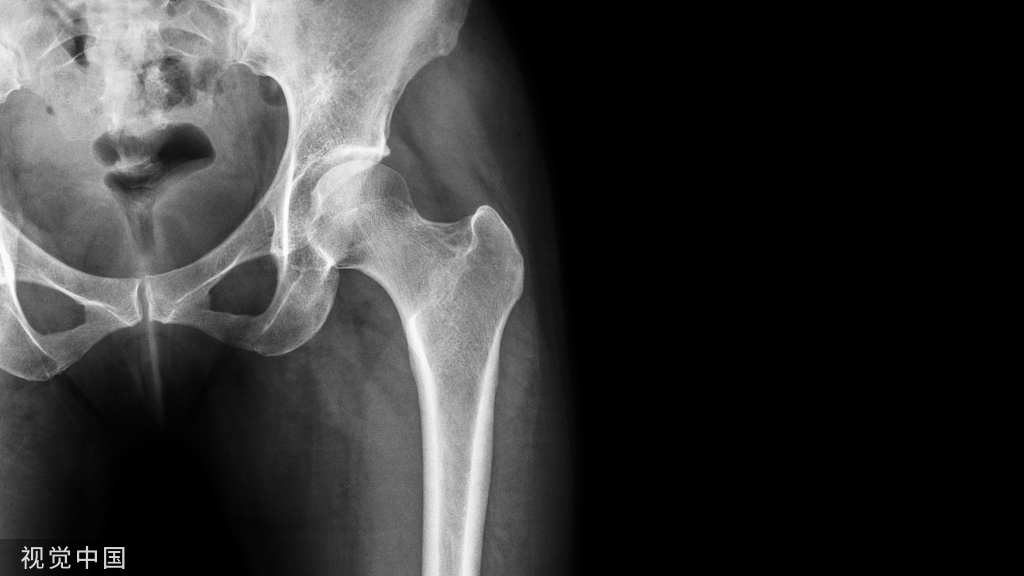

桡骨远端骨折的手法复位及要点!